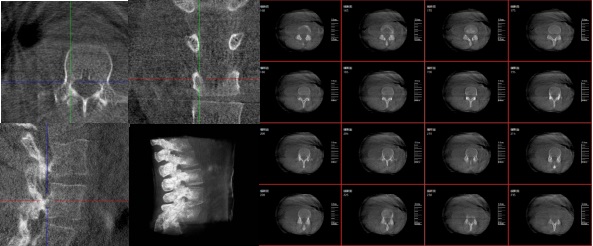

三維重建技術(shù)在醫(yī)學(xué)影像診斷領(lǐng)域十分重要,它是一種利用計算機(jī)軟件將二維醫(yī)學(xué)影像(如X光、CT、MRI等)轉(zhuǎn)化為三維立體圖像的技術(shù),可以為醫(yī)生提供更直觀、更清晰的圖像信息,方便醫(yī)生從多個角度觀察病灶,從而更全面地了解病情,有助于提高診斷的準(zhǔn)確性和效率。

三維重建技術(shù)在醫(yī)學(xué)影像診斷中的應(yīng)用非常廣泛,主要包括以下幾個方面:

1.診斷疾?。和ㄟ^三維重建技術(shù),醫(yī)生可以更直觀、清晰地觀察到患者體內(nèi)的異常情況,如腫瘤、骨折等,從而更準(zhǔn)確地診斷疾病。

2.手術(shù)規(guī)劃:在手術(shù)前,醫(yī)生可以通過三維重建技術(shù)對患者的病變部位進(jìn)行詳細(xì)的觀察和分析,制定出最佳的手術(shù)方案。

3.手術(shù)導(dǎo)航:在手術(shù)過程中,醫(yī)生可以通過三維重建技術(shù)實時觀察手術(shù)器械的位置,提高手術(shù)的精確性和安全性。例如在關(guān)節(jié)外科手術(shù)中,存在植入物的錯位在術(shù)中不易發(fā)現(xiàn)的情況,如果在術(shù)后CT中檢查出,就不可避免地需要翻修手術(shù),這就會增加并發(fā)癥的概率以及感染風(fēng)險。而通過術(shù)中三維影像設(shè)備PLX C7600的檢查,可以立即發(fā)現(xiàn)植入物的錯位,減少不必要的第二次手術(shù)。